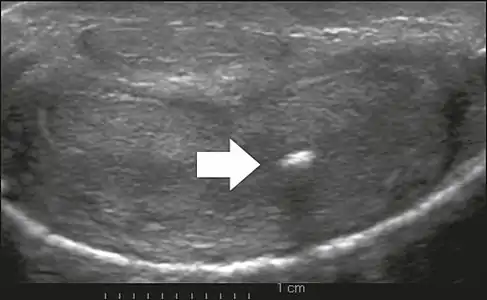

On penile ultrasonography, the typical appearance is hyperechoic focal thickening of the tunica albuginea. Due to associated calcifications, the imaging of patients with Peyronie's disease shows acoustic shadowing, as illustrated in figures below. Less common findings, attributed to earlier stages of the disease (still mild fibrosis), are hypoechoic lesions with focal thickening of the paracavernous tissues, echoic focal thickening of the tunica without posterior acoustic shadowing, retractile isoechoic lesions with posterior attenuation of the beam, and focal loss of the continuity of the tunica albuginea. In the Doppler study, increased flow around the plaques can suggest inflammatory activity and the absence of flow can suggest disease stability. Ultrasound is useful for the identification of lesions and to determine their relationship with the neurovascular bundle. Individuals with Peyronie's disease can present with erectile dysfunction, often related to venous leakage, due to insufficient drainage at the site of the plaque. Although plaques are more common on the dorsum of the penis, they can also be seen on the ventral face, lateral face, or septum.[14]

Transverse ultrasound of the penis, in a ventral view, in the middle portion of the penis. Note the echoic image with posterior acoustic shadowing, corresponding to calcification (arrow), in the left corpus cavernosum.[14]